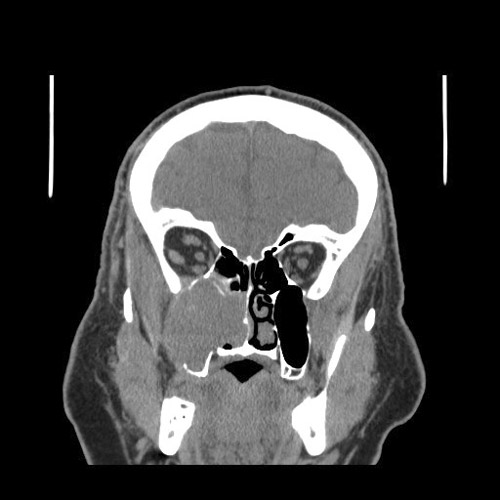

There

was

large destructive mass

(Panel

A)

that

occupied

the bulk of the space of the right maxillary sinus with destruction of the floor

of the orbit and anterior wall of the maxillary sinus. Invasive fungal infection

could

generate this type of picture but the clinical story

did

not go along with it. A malignant tumor

the most likely diagnosis in this case.

The epicenter of the tumor did not seem to be of osseous origin. This made

osseous based tumors such as osteosarcoma and hematopoietic tumors such as

lymphoma and plasmacytoma less likely. With this type of growth pattern and the

location both taken into consideration, an epithelial neoplasm, most likely a

carcinoma, was the leading differential diagnosis.

A. CT |